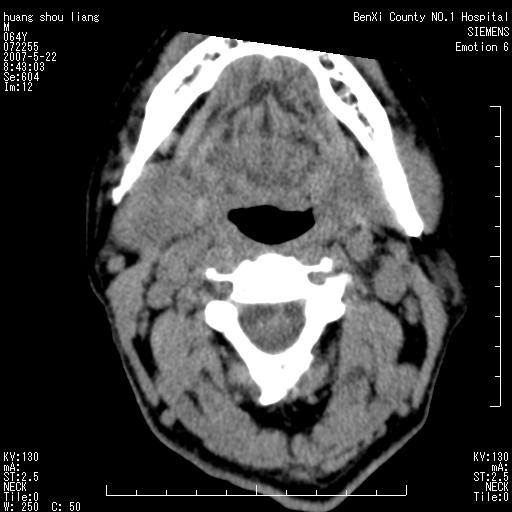

男性,64岁。颈部包块8年。最近增大。

对不起大家,可能是片子发太多有点乱,正常腮腺在下颌角的外侧,颌下腺在下颌体的中部内侧,本例在下颌角内侧偏下,和腺体一点关系都没有,从vrt和mpr上可以很明显看出来,再者肿块是好多粘连在一块的,大家在仔细看看,左侧可能也是吧,我还是考虑为肿大的淋巴结融合在一块,但性质??????

右侧腮腺下部均匀软组织密度肿块,外形不规则,与周围组织分界清晰,考虑右侧腮腺混合瘤或多形性腺瘤。

大家好,病理结果出来了,如大家所说,颌下腺混合瘤。

唉,解剖没学好吧,我诊断错了,不过还是有些不理解回去我在多看看书,谢谢大家的参与,以后我还会奉献好的病例。